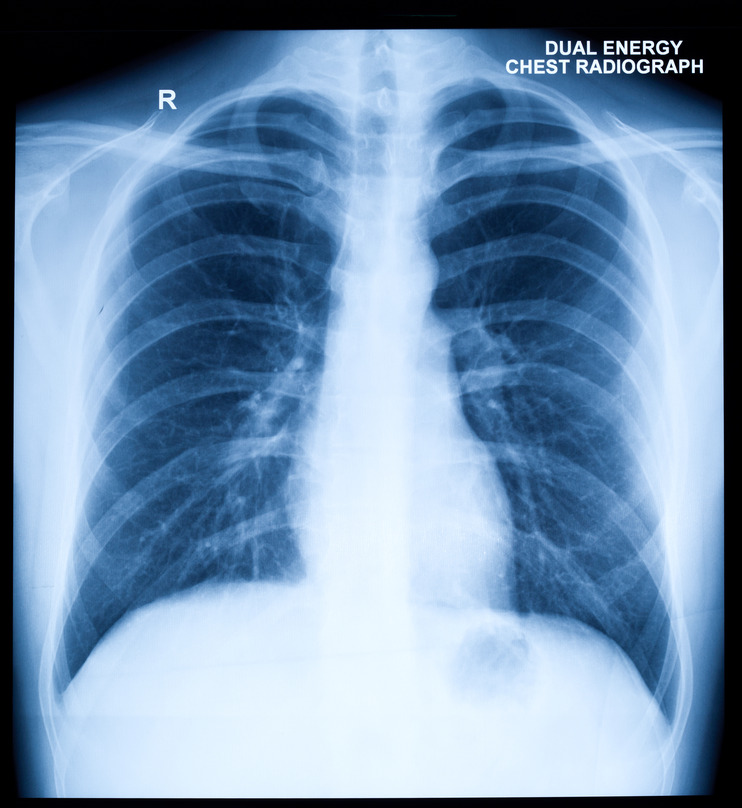

Radiology: Normal Chest X-Rays – Glass Box

glassboxmedicine.comrays radiology cxr coloration

glassboxmedicine.comrays radiology cxr coloration

Normal Chest X-ray - Stock Image - C019/7404 - Science Photo Library

www.sciencephoto.comphotostock photograph seventy 27th similar

www.sciencephoto.comphotostock photograph seventy 27th similar